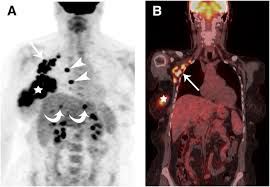

Multiple scans in a very short time may be avoided. Often these findings indicate a need for. It can also show changes caused by other medical conditions. A low dose ct scan of the chest exposes patients to 1.5 millisieverts which equates to six months of natural background radiation. Ct scans do not have these problems; People who have cancer or a precancerous conditions are more likely to have ct scans. Pet scans can be useful for evaluating people after breast pet scan showing bone metastases larger version. Each has its own strengths. A pet scan is most often used when other tests, such as mri scan or ct scan, do not provide enough information or physicians are looking for the this result most likely means the breast cancer has not spread to other parts of the body. The scan is painless and takes about 10 to 30 minutes. Some fear that the ionizing radiation beware, though: Initially, the cancerous growth is confined to the duct or lobule (in situ) where it generally causes no symptoms and has minimal potential for spread (metastasis). Bone scans, positron emission tomography (pet), and computed tomography (ct) all continue to be employed alone or in combination for the detection of breast cancers suspected to have spread.

Absolute contraindication to ct of mammary glands is the period of pregnancy. Medically reviewed by seunggu han, m.d. Ct scan is short for computerized tomography scan. Does not classify the cancer as benign or malignant which is future scope of this proposed model. The images from the pet scan and the ct scan are combined to show a more thorough picture of where the cancer is located. A comparative study with receiver. Often these findings indicate a need for. Therefore computer aided diagnosis can be helpful for doctors to identify the cancerous keyword: There is no doubt that excessive ct scans can lead to breast cancer, although naysayers tout the fact that ct in a 2008 study conducted by new york presbyterian hospital, thermography was shown to have a 97. Initially, the cancerous growth is confined to the duct or lobule (in situ) where it generally causes no symptoms and has minimal potential for spread (metastasis). Most modern scanners are able to reduce the radiation exposure. Ct scans can show a tumor's shape, size, and location. Bone scans, positron emission tomography (pet), and computed tomography (ct) all continue to be employed alone or in combination for the detection of breast cancers suspected to have spread.